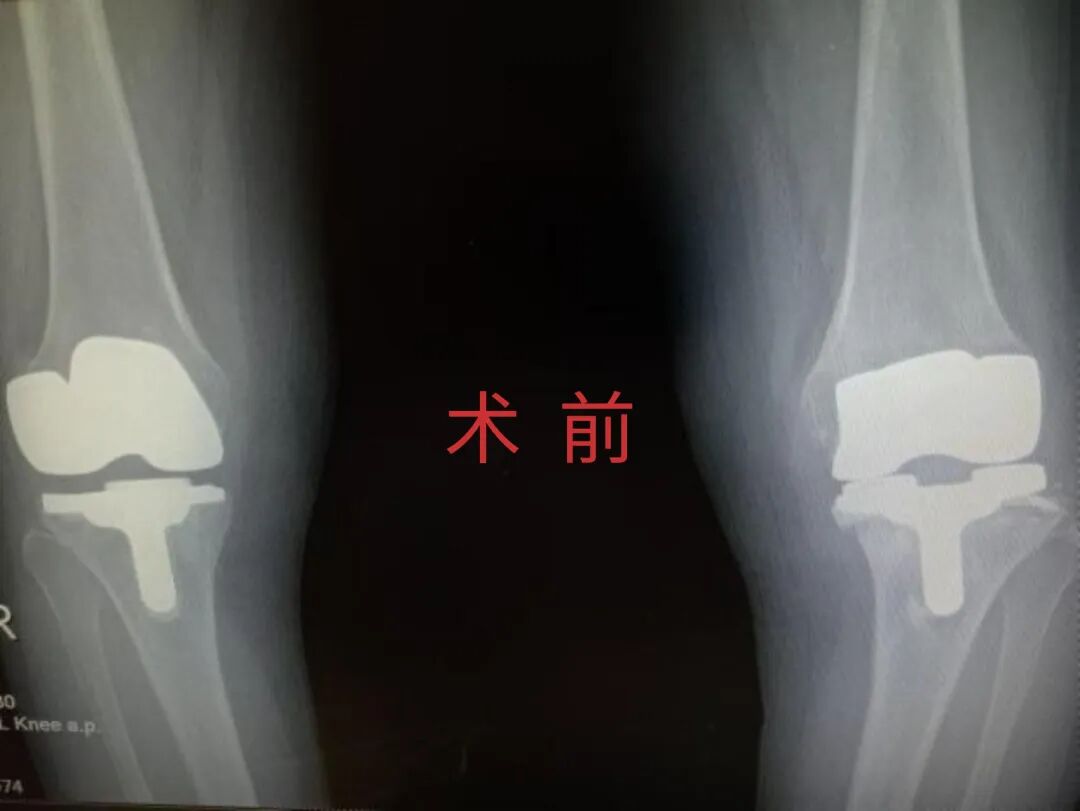

多年来,贵州航天医院各科室紧跟医学前沿,不断强技术、补短板,大力开展新技术、新项目,完成了许多高精尖、高难度、本地区“首例”的技术,填补了医院医疗技术空白,满足了群众日益增长的医疗需求。 贵州航天医院骨科率先在遵义地区开展骨搬移技术,截至目前,已治愈慢性骨髓炎、感染性骨不连、骨缺损、脉管炎、糖尿病足患者200余例,糖尿病足治疗保肢率达到98%。 本期,我们将为大家带来骨科特色技术——骨搬移技术(Ilizarov)。 案例分享 一名59岁的患者,身患糖尿病12年,在来我院3个月前出现了右脚溃烂的症状,来院就诊时,患者的右脚十分红肿,右脚脚趾坏死,伤口处不断流出黑红色脓液,情况十分严重。在接诊到患者时,骨科专家团队高度重视,立刻为患者完善了CT血管造影(CTA)等相关检查,诊断为:2型糖尿病,糖尿病周围血管病变,右糖尿病足。 术 前 考虑到患者情况比较严重,为最大限度保证患者肢体完整,科室专家团队进行了严格的讨论评估,为患者制定了骨搬移技术治疗方案,在征得患者及其家属的同意后,成功通过搬移骨块为患者进行治疗,促进患者病变肢体血管再生。 胫骨横向骨搬移外架固定 清除感染病灶 术后调节外架,通过搬移骨块 促进患肢血管再生 患者在术后三周前来换药,观察到感染得到进一步控制;术后六周复查,患者病变处已愈合,进行CT血管造影(CTA)后可明显观察到足部血管再生。 术后3周 术后6周愈合 CT血管造影见足部血管再生 糖尿病患者全身与局部的问题互为影响,形成恶性循环,糖尿病足溃疡创面迁延不愈,常见干性坏疽、湿性坏疽、趾坏死、深且大的溃疡以及骨髓炎等症状,还可导致脓毒血症,以往为保全生命,患者被迫选择一次或多次截肢。骨搬移技术的发展进步,能在血糖有效控制、局部有效清创下,有效促进患肢微血管再生,改善患肢血供,达到糖尿病足更快治疗康复的目的,并能根据病变情况最大限度的保障患者肢体完整。 什么是骨搬移技术 骨搬移技术是通过使用专用的骨外固定器固定骨段,每天缓慢牵拉,在牵拉搬移过程中,骨段尾部形成新骨及新的软组织,从而修复骨骼缺损及软组织缺损。是治疗大段骨缺损、骨不连、骨感染、肢体畸形的金标准方法,也用于治疗脉管炎、糖尿病足等肢体缺血性疾病。 骨感染缺损 切除感染段 搬移骨段 新骨形成 骨感染根治愈合 骨搬移技术原理 生物组织在持续、稳定、缓慢牵拉下,能刺激细胞分裂、组织再生,骨外固定技术运用该原理,通过持续缓慢调节外固定器形成牵拉张力,促进牵引成骨与相邻组织再生,如神经、血管、肌肉、皮肤等再生,达到治疗大段骨缺损、肢体缺血如糖尿病足等疾病的目的。 骨搬移技术优势 (一)除治疗骨缺损、骨不连外,有更广的适用范围,利用组织再生、血管再生等特性,能大量运用于肢体畸形的矫形、糖尿病足等的治疗。 (二)治疗效果确切,重建肢体外型和功能,极大降低截肢率和残疾率。 (三)明显提高了患者生活质量,极大减轻其家庭及社会负担。 肢体畸形的矫形 慢性骨髓炎 骨段切除 术后1年 濒临截肢的脉管炎术后6周 难愈创面术后3周 贵州航天医院骨科 专家团队 赵学平 骨科主任 主任医师 临床擅长:从事骨科临床工作30余年,对骨科常见疾病的诊治具有丰富的临床经验。 世界中医药联合会脊柱康复专业委员会常务理事,中华中医药学会整脊分会常务委员,中国中西医结合学会骨伤科分会肢体矫形功能重建与康复专家委员会常务委员,中国研究性医院学会骨科创新与转换专业委员会关节外科学组保髋工作委员会常委,中国康复技术转化及发展促进会骨外科与康复技术转化专业委员会常务委员,泛珠三角区域运动医学联盟(PPRD-SMA)理事会常务理事,中国研究型医院学会运动医学专业委员会委员,贵州省中医药学会整脊分会副主任委员,贵州省中西医结合学会银质针专业委员会副主任委员,贵州省康复医学会骨与关节专业委员会常务委员,贵州省人民医院骨科专科联盟常务理事,贵州省康复医学会骨内科专业委员会常务委员,中华医学会贵州省骨科学会委员,贵州省康复医学会脊柱脊髓专业委员会常务委员,贵州省运动医学分会委员,贵州省康复医学会骨与软组织肿瘤专业委员会委员,遵义市医学会创伤分会副主任委员,贵州省康复医学会骨内科专业委员会遵义地区分会常务委员,遵义市医疗事故鉴定、伤残鉴定、工伤鉴定、司法鉴定专家。 长期从事骨科临床研究及教学工作,在国家级、省部级杂志发表论文20余篇,SCI论文2篇,参与主编骨科专著2部,主持省部级科研项目2项,参与指导省部级、市级科研项目6项。 陈明勇 骨科副主任 副主任医师 临床擅长:从事创伤骨科工作约20年,对骨缺损、骨不连、骨肿瘤、肢体畸形等的肢体矫形重建及功能重建,慢性化脓性骨髓炎的根治治疗、糖尿病足的保肢治疗、快速康复理念(ERAS)下的老年骨折的诊治,四肢复杂骨折的诊治,四肢骨折等微创手术治疗具有丰富的临床经验。 2004年毕业于遵义医学院临床专业,曾在中国人民解放军总医院、广西医科大学第一附属医院、上海第六人民医院骨科进修。中国中西医结合学会骨伤科专业委员会横向骨搬移治疗糖尿病足及微血管网再生学组首届委员,遵义市医学会创伤分会常务委员。 瞿 辉 骨科 副主任医师 临床擅长:对骨科的常见病、关节外科、脊柱外科及运动医学疾病的诊治具有丰富的临床经验,熟练掌握骨科手术操作技术。 毕业于遵义医学院临床医学系,2005年前往广州中山大学第一附院骨显微医学部进修学习,2011年前往成都华西医院进修学习,并多次在省内外学习骨科相关知识,是中华医学会骨科分会会员。 赵兴东 骨科 主任医师 临床擅长:擅长骨科的常见病及各种创伤、四肢骨折创伤修复、骨感染、手足疾病的诊治和手足体表畸形的矫形整复,熟练掌握骨科四肢骨病及创伤的手术操作技术,尤其在四肢关节复杂性损伤、手足外伤、组织缺损创面、难治创面的皮瓣修复方面及平足、高弓足矫形方面及四肢慢性疼痛诊治、康复方面具有丰富的临床经验。 硕士研究生,毕业于遵义医学院临床外科系,2015年前往山东省立医院手足外科进修学习;遵义市医学分会创伤分会第一、二届委员,遵义市手外科医学会第二委届员会常务委员;在省级及省级以上期刊发表文章9篇,参编著作2部,参与主持并完成市级课题1项,参与市级课题2项、省级课题1项。 张俊凯 骨科 副主任医师 临床擅长:从事骨科临床工作28年,对创伤骨折、骨感染、骨缺损、骨不连等外科诊治,四肢骨折的微创手术治疗,四肢复杂骨折(如关节内粉碎性骨折、多发骨折等)的损伤控制及手术治疗等具有丰富的临床经验。 1995年毕业于遵义医学院临床专业,2009年前往复旦大学附属医院骨科进修1年。 卢懿明 骨科 副主任医师 临床擅长:从事骨科工作18年,对创伤骨折、四肢骨折的微创手术治疗、四肢复杂骨折(如关节内粉碎性骨折、多发骨折等)的损伤控制及手术治疗,尤其是髋部骨折的PFNA等微创技术,踝关节骨折、膝关节周围骨折的Mipo微创技术等具有丰富的临床经验,开展了4项新技术,发明6项新型专利技术。 2005年毕业于遵义医学院临床专业,2017年,前往南方医科大学第三附属医院骨科进修半年,回院后运用Mipo技术对骨干骨折及干骺端骨折的治疗技术,同时积极开展骨盆骨折、髋臼骨折腹直肌外侧切口的应用;发表了多篇专业论文,经常参与省内外学术交流会授课,获得医院荣誉称号多个。 邬夏荣 骨科 副主任医师 临床擅长:从事骨科工作16年,对四肢复杂骨折、骨肿瘤的诊治,尤其是足踝创伤、慢性踝关节损伤、平足症等诊疗具有丰富的临床经验。 2006年毕业于遵义医科大学临床医学专业,曾在陆军军医大学西南医院进修学习,发表多篇骨科学术论文。 余德怀 骨科 副主任医师 临床擅长:从事骨科工作10余年,对运动医学、骨关节、脊柱外科常见病、多发病的诊治具有丰富的临床经验。 硕士研究生,2011年毕业于遵义医学院临床医学专业,曾前往遵义医科大学附属医院运动医学专业进修学习;是贵州省医学会运动医学分会青年委员,西部关节镜联盟委员;发表多篇骨科学术论文。 冯 乾 骨科 副主任医师 临床擅长:从事骨科工作近20年,熟练掌握骨科多发病及常见病的诊治,尤其对脊柱退变性疾病的诊断及治疗具有丰富的临床经验,主要研究脊柱微创相关治疗方式,能熟练开展椎间孔镜及VBE。 曾前往北京大学第三医院进修学习疼痛及椎间孔镜、首都医科大学友谊医院专业进修脊柱内镜;是贵州省康复医学会第三届脊柱脊髓专业委员会委员;发明专利3项、发表脊柱外科专业论文多篇。 张艳金 骨科 副主任医师 临床擅长:从事骨外科工作16年,对复合伤、多发伤的救治、四肢骨干骨折、关节周围骨折、骨肿瘤、骨髓炎等诊治具有丰富的临床经验。 中共党员,硕士研究生,2006年本科毕业于山西医科大学第二临床医学院,2011年研究生毕业于北京军区总医院;在“老年COPD患者合并髋部骨折的诊治”国际合作课题组研究两年,在老年髋部骨折的诊治方面具有丰富的经验,并发表论文6篇;承担遵义市级课题1项;承担遵义医科大学的临床教学工作,获得遵义医科大学优秀带教老师荣誉。编撰有《骨科疾病诊疗精粹》一书,开展2项新技术,编撰地方规范《务川自治县创伤骨科常见疾病诊疗规范》一书。 赵小锋 骨科 副主任医师 临床擅长:从事骨科临床工作11年,对骨科常见病、多发病诊疗有较为丰富的临床经验,擅长脊柱相关疾病诊断及治疗,尤其是颈、腰、腿疼痛疾病诊断及治疗,擅长胸腰椎骨折微创经皮穿刺内固定术、经皮穿刺椎体成形术、经皮穿刺脊柱内镜下腰椎间盘摘除术、单纯开创腰椎间盘摘除术、腰椎滑脱复位椎间植骨椎融合内固定术、腰椎管狭窄减压融合内固定术及人工髋、膝关节置换术等。 2012年毕业于遵义医学院外科学专业硕士研究生,2019年参加“遵义市115医学人才精英计划”于上海交通大学第一附属医院培训学习,2023年于北京大学第三人民医院脊柱外科进修学习,曾获得遵义市优秀医师荣誉称号。 遵义市手外科第一届委员,遵义市医学会创伤分会第一届委员,遵义市医学会创伤分会第二届委员,贵州省康复医学会第三届脊柱脊髓专业会委员,遵义市医学会烧伤与整形外科学分会委员,发表论文5篇,其中国家级核心期刊1篇,SCI论文1篇,主持市级课题1项并结题,参与市级课题2项。 贵州航天医院骨科简介 基本情况 贵州航天医院(原3417医院)骨科组建于1968年,前身是以创伤和断肢(断指)再植闻名于世的上海市第六人民医院骨科,中国断肢(断指)再植的奠基者、中科院院士陈仲伟等著名专家、学者多次莅临科室指导医疗、教,是贵州省最早拥有专业骨科技术科室之一,在70年代开展了贵州省首例断肢(断指)再植手术。组建50余年来,诊治患者已逾百万,挽救了无数的伤病员,成为了保障遵义地区人民群众健康的重要支撑。 经过几代人的不懈努力,今天的骨科,已由创伤骨科发展至骨病、骨肿瘤、骨结核等领域,现有脊柱外科、关节外科、四肢创伤、手足外科四个亚专科,成为了集医疗、教学、科研于一体的综合学科,是贵州省临床重点专科、遵义市临床重点专科、遵义市骨科临床医学中心、遵义市基层骨科专科联盟理事长单位。 科室目前开放床位110张,共有医护人员50余人,副高级以上专家18人,硕士研究生15人。拥有一流骨科医疗设备多台,每年不定期选派优秀技术骨干到全国各大知名医学院校进修、学习、参观、交流,并邀请国内、国外知名专家教授来院进行交流、指导,通过不断引进国内外先进的诊疗技术,科室医疗技术水平稳步提升,为广大人民群众提供了优质的医疗服务。 专科特色 骨一科 (一)骨缺损、骨不连的肢体与功能重建 胫骨横向骨搬移技术治疗糖尿病足: (二)慢性骨髓炎的根治治疗 (三)肢体缺血性疾病如糖尿病足、脉管炎的保肢治疗 (四)皮瓣修复 (五)复杂创伤的治疗 (六)老年髋部骨折及小儿骨折快速手术 老年髋部骨折: 骨二科 (一)胸腰椎骨折微创经皮椎弓根螺钉固定术 (二)老年性骨质疏松性患者腰椎滑脱脊柱内固定术(骨水泥螺钉) (三)V形双通道脊柱内镜技术(VBE)腰椎融合术治疗腰椎退行性疾病 (四)老年性骨质疏松性骨折(PVP/PKP)术 (五)人工髋关节置换术 (六)双侧股骨头坏死人工全髋关节置换 (七)右侧全髋置换术后假体周围骨折翻修 (八)人工膝关节置换术 (九)人工膝关节假体松动翻修 (十)关节镜技术 传统手术切口 关节镜技术切口 诊疗范围 骨一科 1.四肢创伤、矫形。 2.手、足踝外科。 骨二科